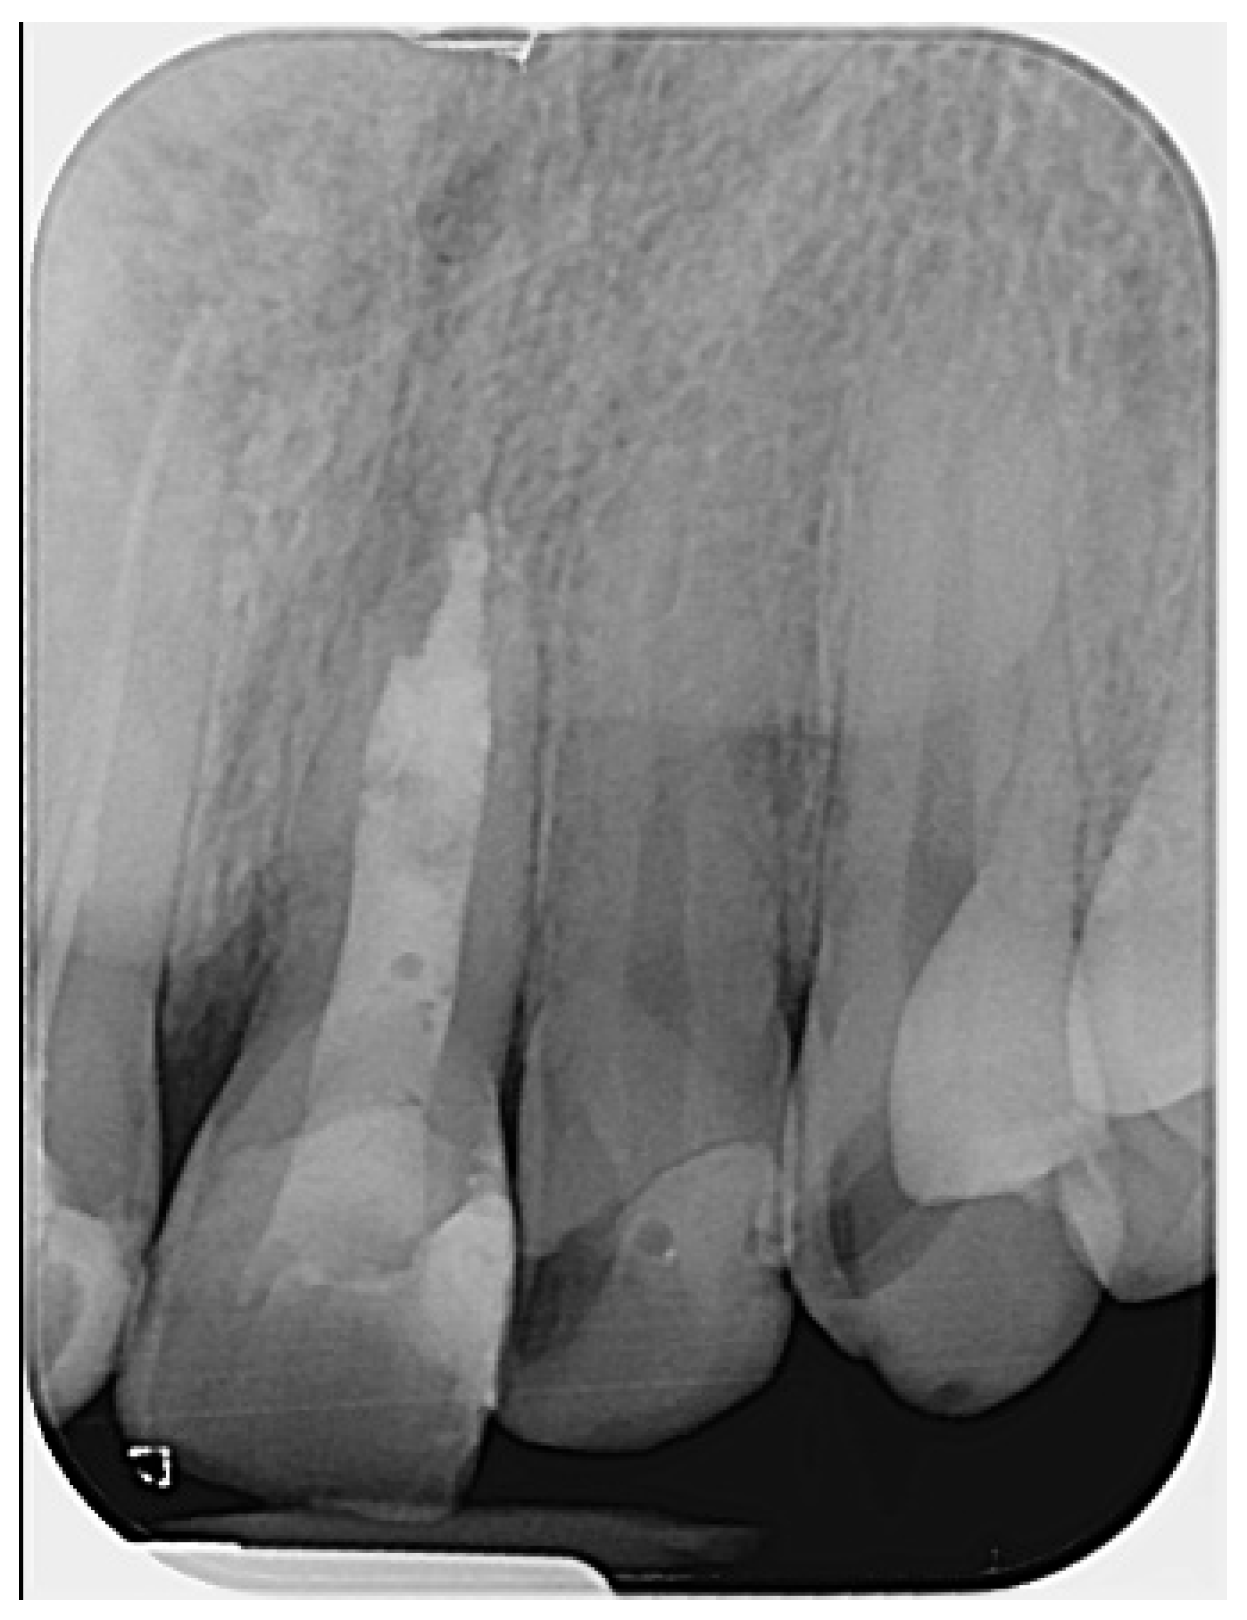

Figure 1. Preoperative radiograph of tooth #21. The radiograph shows previous endodontic treatment, with the root canal filling material not extending to the full length of the canal. A diffuse radiolucency is visible around the open apex. (The mark in the lower left corner indicates the left side).

The periapical radiograph showed that tooth #21 had undergone previous endodontic treatment. A diffuse periapical radiolucency was observed surrounding the open apex. Additionally, the root appeared relatively short and exhibited thinner dentinal walls compared to the adjacent tooth #11 (Figure 1).